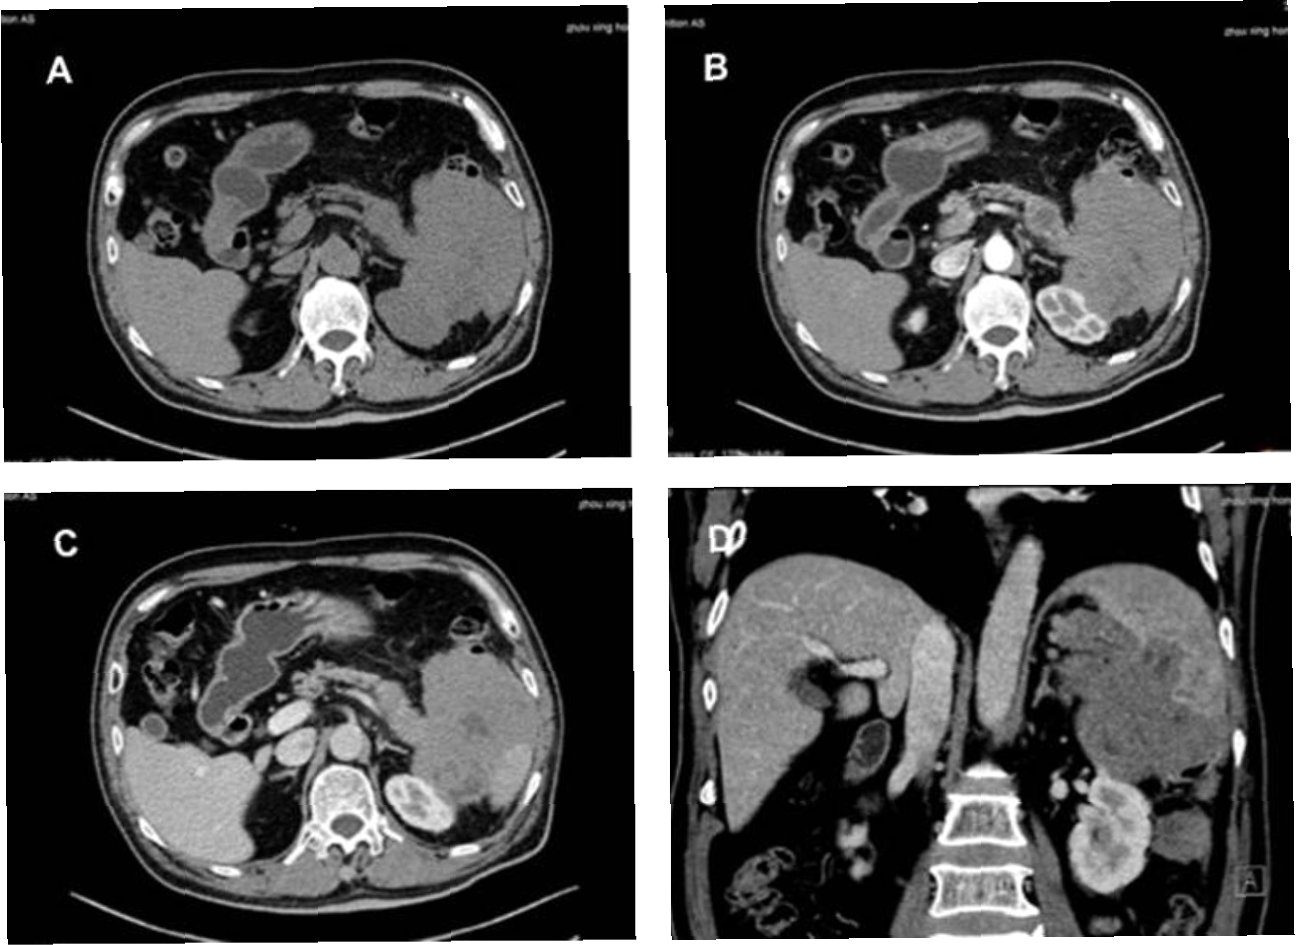

그러다 임신 14주 차 직장에서 쓰러져 병원으로 실려간 뒤 정밀검사에서 원발성 종격동 B세포 림프종(Primary Mediastinal B-cell Lymphoma, PMBCL)을 진단받았다. 종양은 심장 크기만큼 자라 있었고, 빠르게 진행되는 특성상 즉각적인 항암치료가 필요했다. 항암제를 투여할 경우 태아 생존은 불가능했다.

소피아가 진단받은 원발성 종격동 B세포 림프종(PMBCL)은 비교적 드문 형태의 혈액암으로, 비호지킨 림프종의 아형에 속한다. 이 암은 면역세포인 B세포에서 발생하며 주로 가슴 중앙부에 위치한 종격동에서 발병한다.